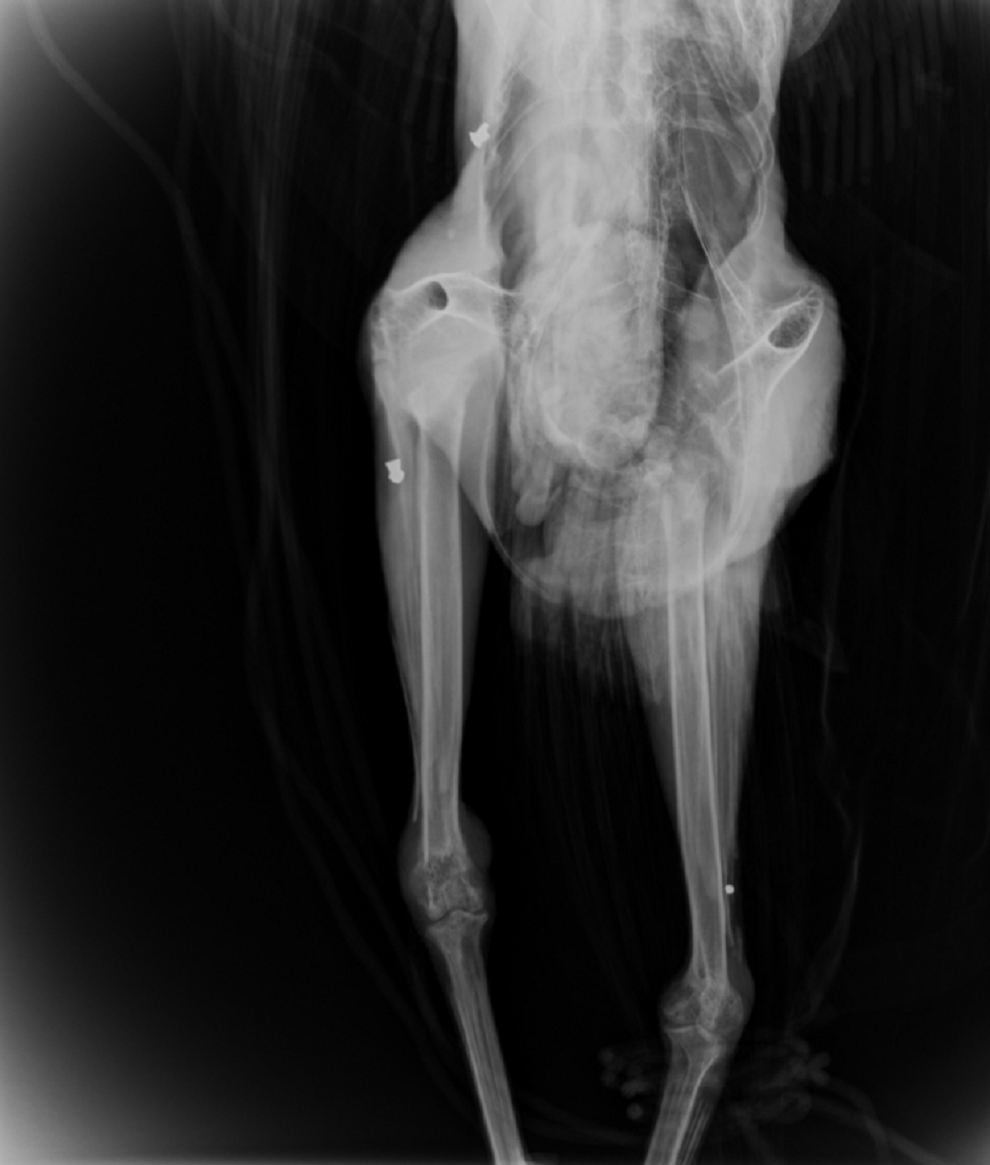

Ο σύλλογος ΑΝΙΜΑ έκανε ανάρτηση στο Facebook, δημοσιεύοντας φωτογραφίες με το τραυματισμένο ζώο και από τις ακτινογραφίες του, ενώ έγραψε το εξής:

«Ένα παγώνι από τον αρχαιολογικό χώρο της Κνωσού στάλθηκε μέσω του Μουσείου Φυσικής Ιστορίας Κρήτης, επειδή κούτσαινε εδώ και λίγο καιρό.

Με έκπληξή μας, εμφανίζοντας την ακτινογραφία, είδαμε δυο βολίδες αεροβόλου κι ένα σκάγι μέσα στο σώμα του!

Το ζώο αυτό έχει πυροβοληθεί τρείς φορές, την ίδια ώρα ή διαφορετικές δεν μπορούμε να ξέρουμε, ούτε αν ο δράστης είναι ένας ή δύο ή τρεις, μέσα ή δίπλα σε έναν από τους πιο πολυσύχναστους αρχαιολογικούς χώρους της Κρήτης και της Ελλάδας γενικότερα».

Ακολουθούν φωτογραφίες: